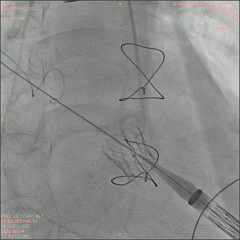

2025年6月4日,在全身麻醉下,通过TEE和荧光镜引导进行手术。通过右颈内静脉建立临时起搏。经左前外侧小切口暴露第五肋间隙,使用双重荷包缝合固定心尖;静脉注射肝素使活化凝血时间(ACT)>250秒。心尖穿刺后,先使用软导丝穿过主动脉瓣口,随后更换为Amplatz超硬导丝(波士顿科学公司)。在快速起搏(180次/分)下,使用18mm球囊对主动脉瓣生物假体进行预扩张。选择21mm ScienCrown瓣膜,旋转手柄将瓣膜从输送系统中逐步释放(视频1)。瓣膜成功植入后,无错位或瓣周漏(PVL)(图2B及视频2)。TEE显示主动脉瓣平均跨瓣压差为6mmHg,无瓣周漏(图2C及D)。随后,使用硬导丝穿过二尖瓣生物瓣进入左心房(视频3)。在快速起搏(180次/分)下于二尖瓣位置植入25mm ScienCrown瓣膜(图2E及视频4)。TEE显示二尖瓣平均跨瓣压差为5mmHg,瓣叶运动正常,无瓣周漏(图2F)。术后荧光检查显示两枚瓣膜均位置良好(图2G)。术后第一天床旁TTE显示二尖瓣压差2.52mmHg,流速0.76m/s;主动脉瓣压差13.39mmHg,流速1.7m/s,提示轻度主动脉瓣狭窄(AS)和正常二尖瓣功能(图3)。患者心功能改善至NYHA II级,并在术后第5天出院。

图2. 使用ScienCrown瓣膜进行经心尖主动脉瓣和二尖瓣ViV手术。A:18mm球囊对主动脉瓣进行预扩张。B:成功植入21mm ScienCrown瓣膜,显示无瓣周漏。C:植入后TEE确认无瓣周漏。D:术后TEE记录主动脉瓣平均跨瓣压差为6mmHg。E:二尖瓣位置25mm ScienCrown瓣膜的理想释放。F:植入后TEE评估显示二尖瓣平均跨瓣压差为5mmHg。G:术后影像学检查显示两枚植入假体瓣膜的位置及形态均正常。